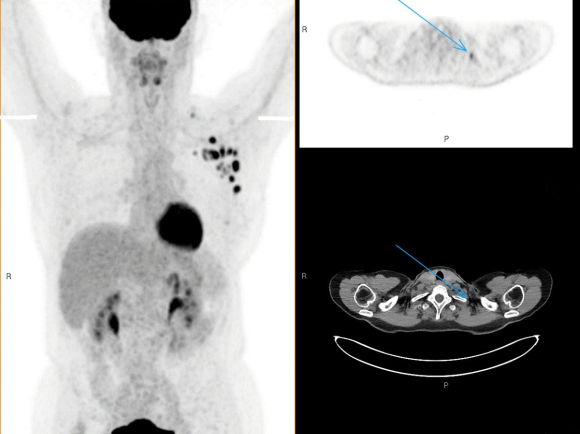

Value of [18F]FDG PET/CT in the work-up to neoadjuvant systemic therapy in breast cancer

L.E.W. Raaijmakers, J. Tol, P.C. Barneveld, M. Bessems